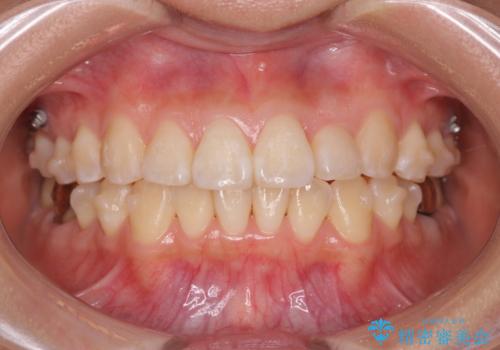

正中のズレ、引っ込んだ前歯の矯正

- 噛んだ時の前歯正中のズレ、引っ込んでいる前歯を治したい。と矯正治療を希望され来院されました。

左上2の前歯はスペースが足りないため、後方に引っ込んでしまっている状態です。

マウスピース矯正システムインビザラインで歯の後方移動、咬合関係の修正を行ったのち、引っ込んでいる左上2をワイヤーを用いて短時間で引き出す治療計画としました。

部分ワイヤー矯正を行なったことで約3ヶ月という短期間で前歯を綺麗に並べることができました。